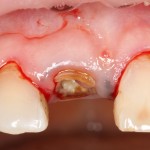

Все началось с воспаления, свищевого хода и удаления зуба:

Затем, мы готовим лунку и проверяем позиционирование импланта:

После чего аугментируем лунку. Для упаковки Bio-Oss Collagen очень удобно использовать аналоги имплантов:

Устанавливаем имплантат XiVE (Dentsply Implants):